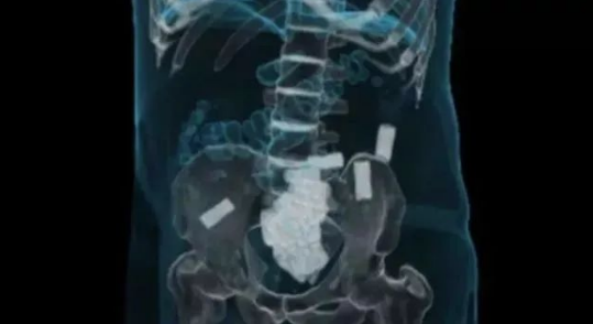

调查后,法医在他的胃部发现209袋包装好的单颗摇头丸,其中79包在他的体内破裂,造成他瞬间吸收大量摇头丸,急性中毒死亡。

但除此之外,他的肠道内还有118克被包裹在避孕套中的氯胺酮粉(K他命),这是一种睡眠麻醉剂,如果作为毒品使用,足以供600人服用。